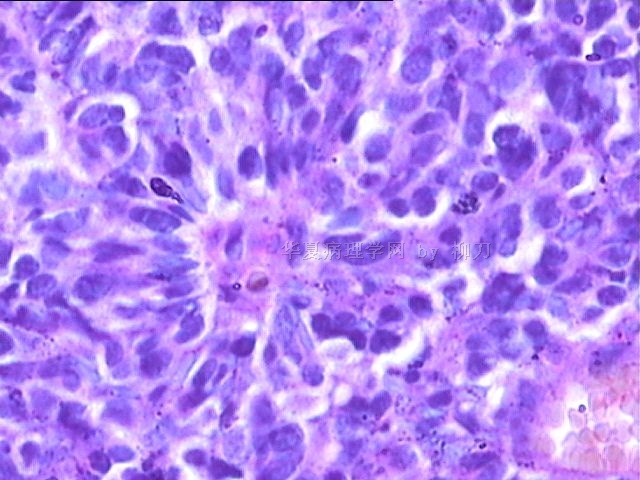

女,34y,头痛一月,右额叶占位:5*5*4cm。囊性区域,4cm。大体:3.5x3x1cm灰白间暗褐色组织一堆,质嫩。临床诊断1:胶质瘤,2:血管母细胞瘤。

本人县级医院头颅手术少,考虑胶质母细胞瘤。大家指导指导。

胶母

同意胶质母细胞瘤。细胞异型、坏死、核分裂、血管内皮肿胀增生均可见到。

This is certainly a WHO grade IV malignant neoplasm. While most likely a glioblastoma, I would carefully rule out PNET by staining for GFAP and neuronal markers such as synaptophysin, NeuN and NSE. Rarely, PNET may shows marked pleomorphism and indistinguishable from glioblastoma on HE stain.

同意马老师的意见,该肿瘤从形态及年龄来看考虑PNET或GBM,须标记Syn、NSE、S-100、NeuN和GFAP来鉴别。

结合图片细胞形态特点考虑胶质母细胞瘤,组化标记排除其他